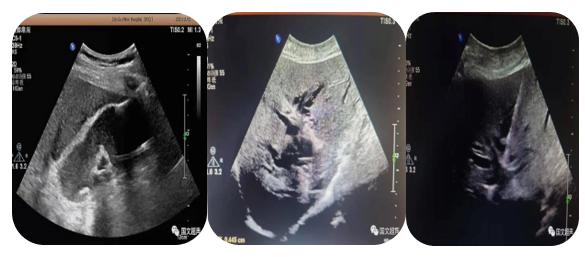

4.超聲介導(dǎo)下肝占位射頻及微波消融術(shù)

通過(guò)射頻電極發(fā)出高頻率射頻電流,電能使局部組織發(fā)生正負(fù)離子震蕩,并摩擦生熱達(dá)100°左右,熱能逐漸傳導(dǎo)至周?chē)M織,形成一個(gè)預(yù)定的球形或類(lèi)球形的消融區(qū),腫瘤局部因高溫而發(fā)生凝固壞死。以達(dá)到和手術(shù)切除同樣的目的和效果。

5.超聲介導(dǎo)下囊腫硬化治療

局部麻醉患者清醒狀態(tài)超聲直視下穿刺針進(jìn)入囊腫囊腔內(nèi)抽出囊液,注入硬化劑,手術(shù)時(shí)間短,損傷輕微,痛苦小,安全性高。